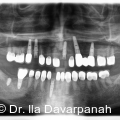

Die moderne Implantologie vereint heute funktionelle Stabilität mit höchsten ästhetischen Ansprüchen. Gerade im Frontzahnbereich hängt der Behandlungserfolg entscheidend von der präzisen Planung, der gewebeschonenden chirurgischen Umsetzung und einer frühzeitigen prothetischen Integration ab. Fotos: © Dr. Ila Davarpanah